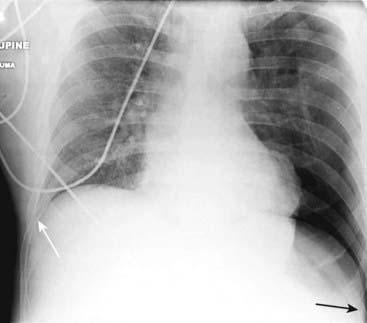

Figure 8-4 Deep sulcus sign.

In the supine position, air in a relatively large pneumothorax may collect anteriorly and inferiorly in the thorax and manifest itself by displacing the costophrenic sulcus inferiorly while, at the same time, producing increased lucency of that sulcus (solid black arrow). This is called the deep sulcus sign and is an indication of a pneumothorax on a supine radiograph. Notice how much lower the left costophrenic sulcus appears than the right sulcus (solid white arrow).

Figure 8-11 Bilateral pneumothoraces.

Conventional radiography is the initial modality used for detecting pneumothorax, but smaller pneumothoraces may be visible only on CT scans of the chest. This patient has bilateral pneumothoraces (solid white arrows). Air will rise to the highest point (the patient is supine in the CT scanner). Extensive subcutaneous emphysema also is present (solid black arrows); it developed because of an “air leak” from a chest tube that had been inserted earlier.